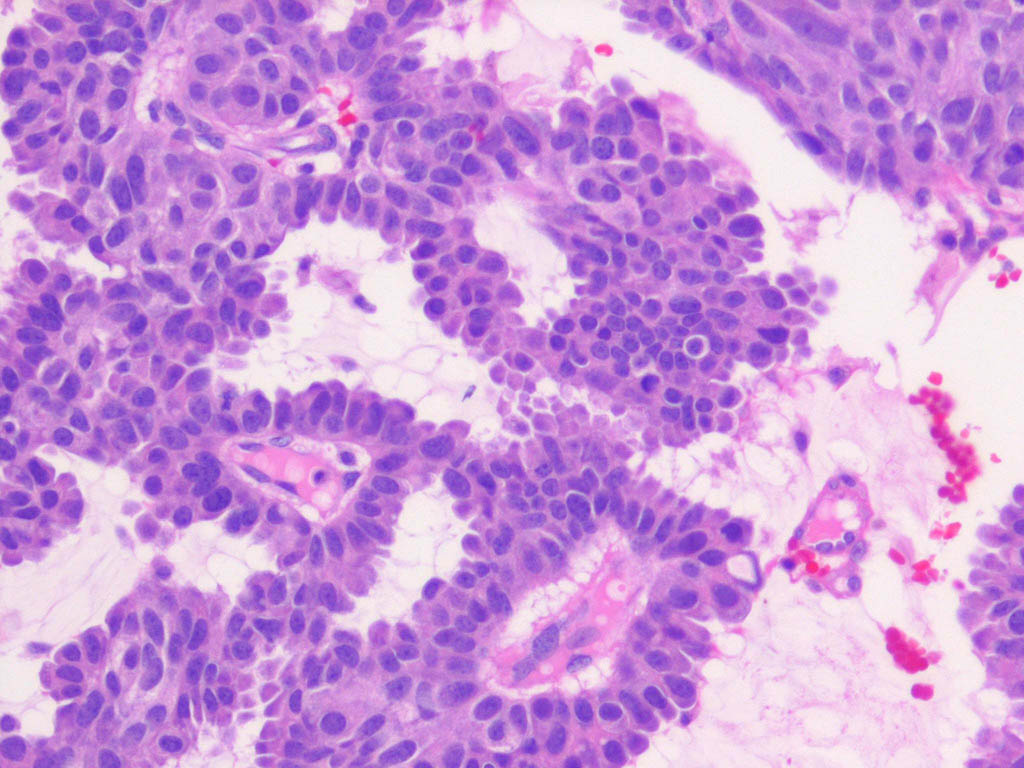

Hidradenoma papilliferum = الغدوم العرقي الحليمي